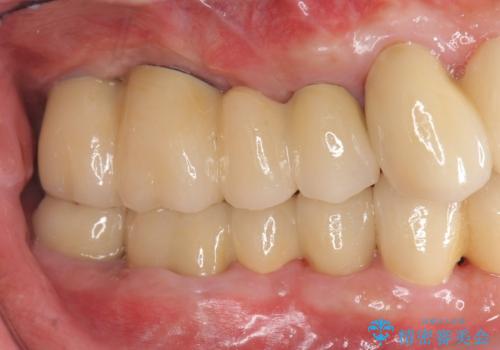

くいしばりで割れたブリッジの支台歯 インプラント再補綴

- 「数年前に入れたブリッジがぐらぐらする、診て欲しい。」と来院されました。

ブリッジを支える歯が割れてしまい、抜歯が必要であることと、骨の大きな吸収が見られました。

インプラント治療を行うにあたり周囲に骨を造成することで安定して噛める環境の整備を計画します。

今回はインプラント埋入時に固定が得られたので同時に骨の造成を行い治療を進めることができました。